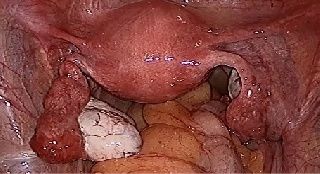

The rate of laparoscopic hysterectomy has greatly increased over the past decade and is now higher than that of abdominal hysterectomy, according to a study in the April issue of the American Journal of Obstetrics and Gynecology.This study with firm statistical believe has confirms that rates of laparoscopic minimal invasive procedures for hysterectomy have within past 10 year has also been dramatically increased in metro city of India also. At our World Laparoscopy Hospital also, over the last decade we have almost stopped performing open hysterectomy which is consistent with other reports in the literature. This change in trend towards laparoscopy is likely is due to an increase in the number of laparoscopic surgical and gynecological procedures being performed over the last few years, increasing the skill of laparoscopic surgeons as well as the ability of our study to capture Laparoscopic Hysterectomy as the demand of patient has shifted towards this. Our unique ability to determine hysterectomy route, which predates appropriate skill of more and more gynecologists may provide a more accurate characterization of hysterectomy trends.

In recent years, more women have opted for a laparoscopic procedure, rather than surgery through a large abdominal incision or traditional vaginal surgery, in which a doctor manipulates surgical instruments through small incisions in the abdomen. Robot-assisted hysterectomy surgery is also increased in number and result is similar to the conventional laparoscopic technique. But the procedure of da Vinci robotic surgery is performed by a robotic surgeon sitting at a console some distance from the operating table and da Vinci console who uses hand and foot controls to manipulate four arm da Vinci surgical tools that are attached to a robot arms. Proponents of da Vinci robot-assisted surgery say that it can be a good minimally invasive option when surgeries are complex and can result in less blood loss, pain and a quicker return to normal life than traditional open surgery. But it is also more costly so those with private insurance were significantly more likely to undergo laparoscopic surgery than patients on Medicare or Medicaid or the uninsured .

Laparoscopic surgery has become increasingly popular over the past few decades due to its several advantages over traditional open surgery. Laparoscopic surgery involves making small incisions in the patient's body and inserting a camera and surgical instruments through the incisions. The use of robotic systems, such as the da Vinci robotic system, has further improved the precision and accuracy of laparoscopic surgery. One of the most common laparoscopic procedures performed using the da Vinci robotic system is hysterectomy. This essay will discuss the increase in the number of laparoscopic da Vinci robotic hysterectomies performed over the past decade and the benefits of this surgical technique.